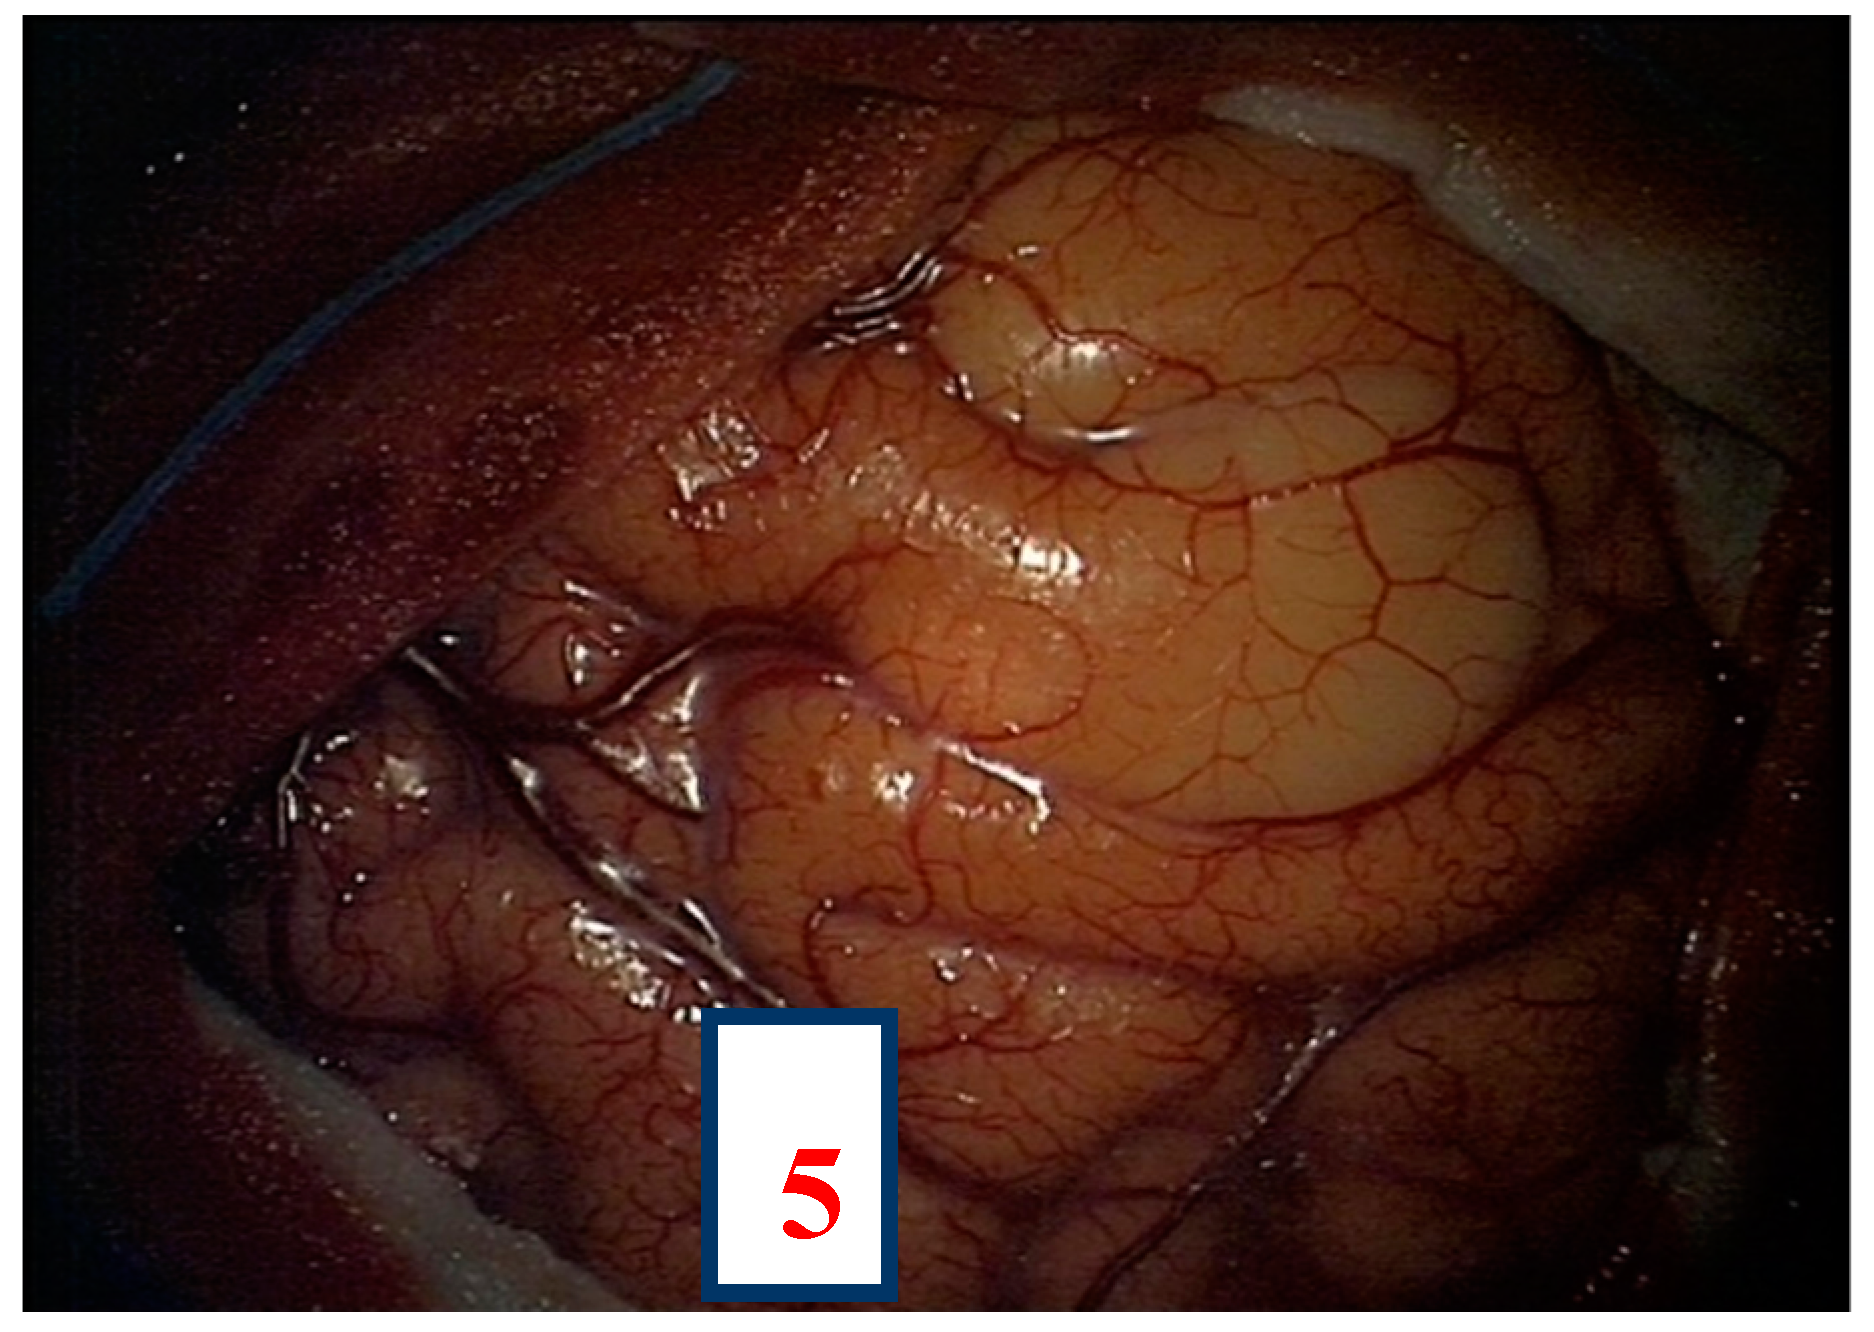

After navigation-guided identification of the tumour boundaries, an “awake” resection was performed and intraoperative identification of Broca’s area (tag 5) with “speech arrest” and inferior fronto-occipital fascicle (IFOF) with transient fonemic paraphasia was reached (tag 8) Figure 2, Figure 3 and Figure 4. Resection was then stopped.

Figure 3. Intra-operative picture showing Broca’s area (number 5) identified by direct electrical stimulation.

Brainsci 08 00192 g003